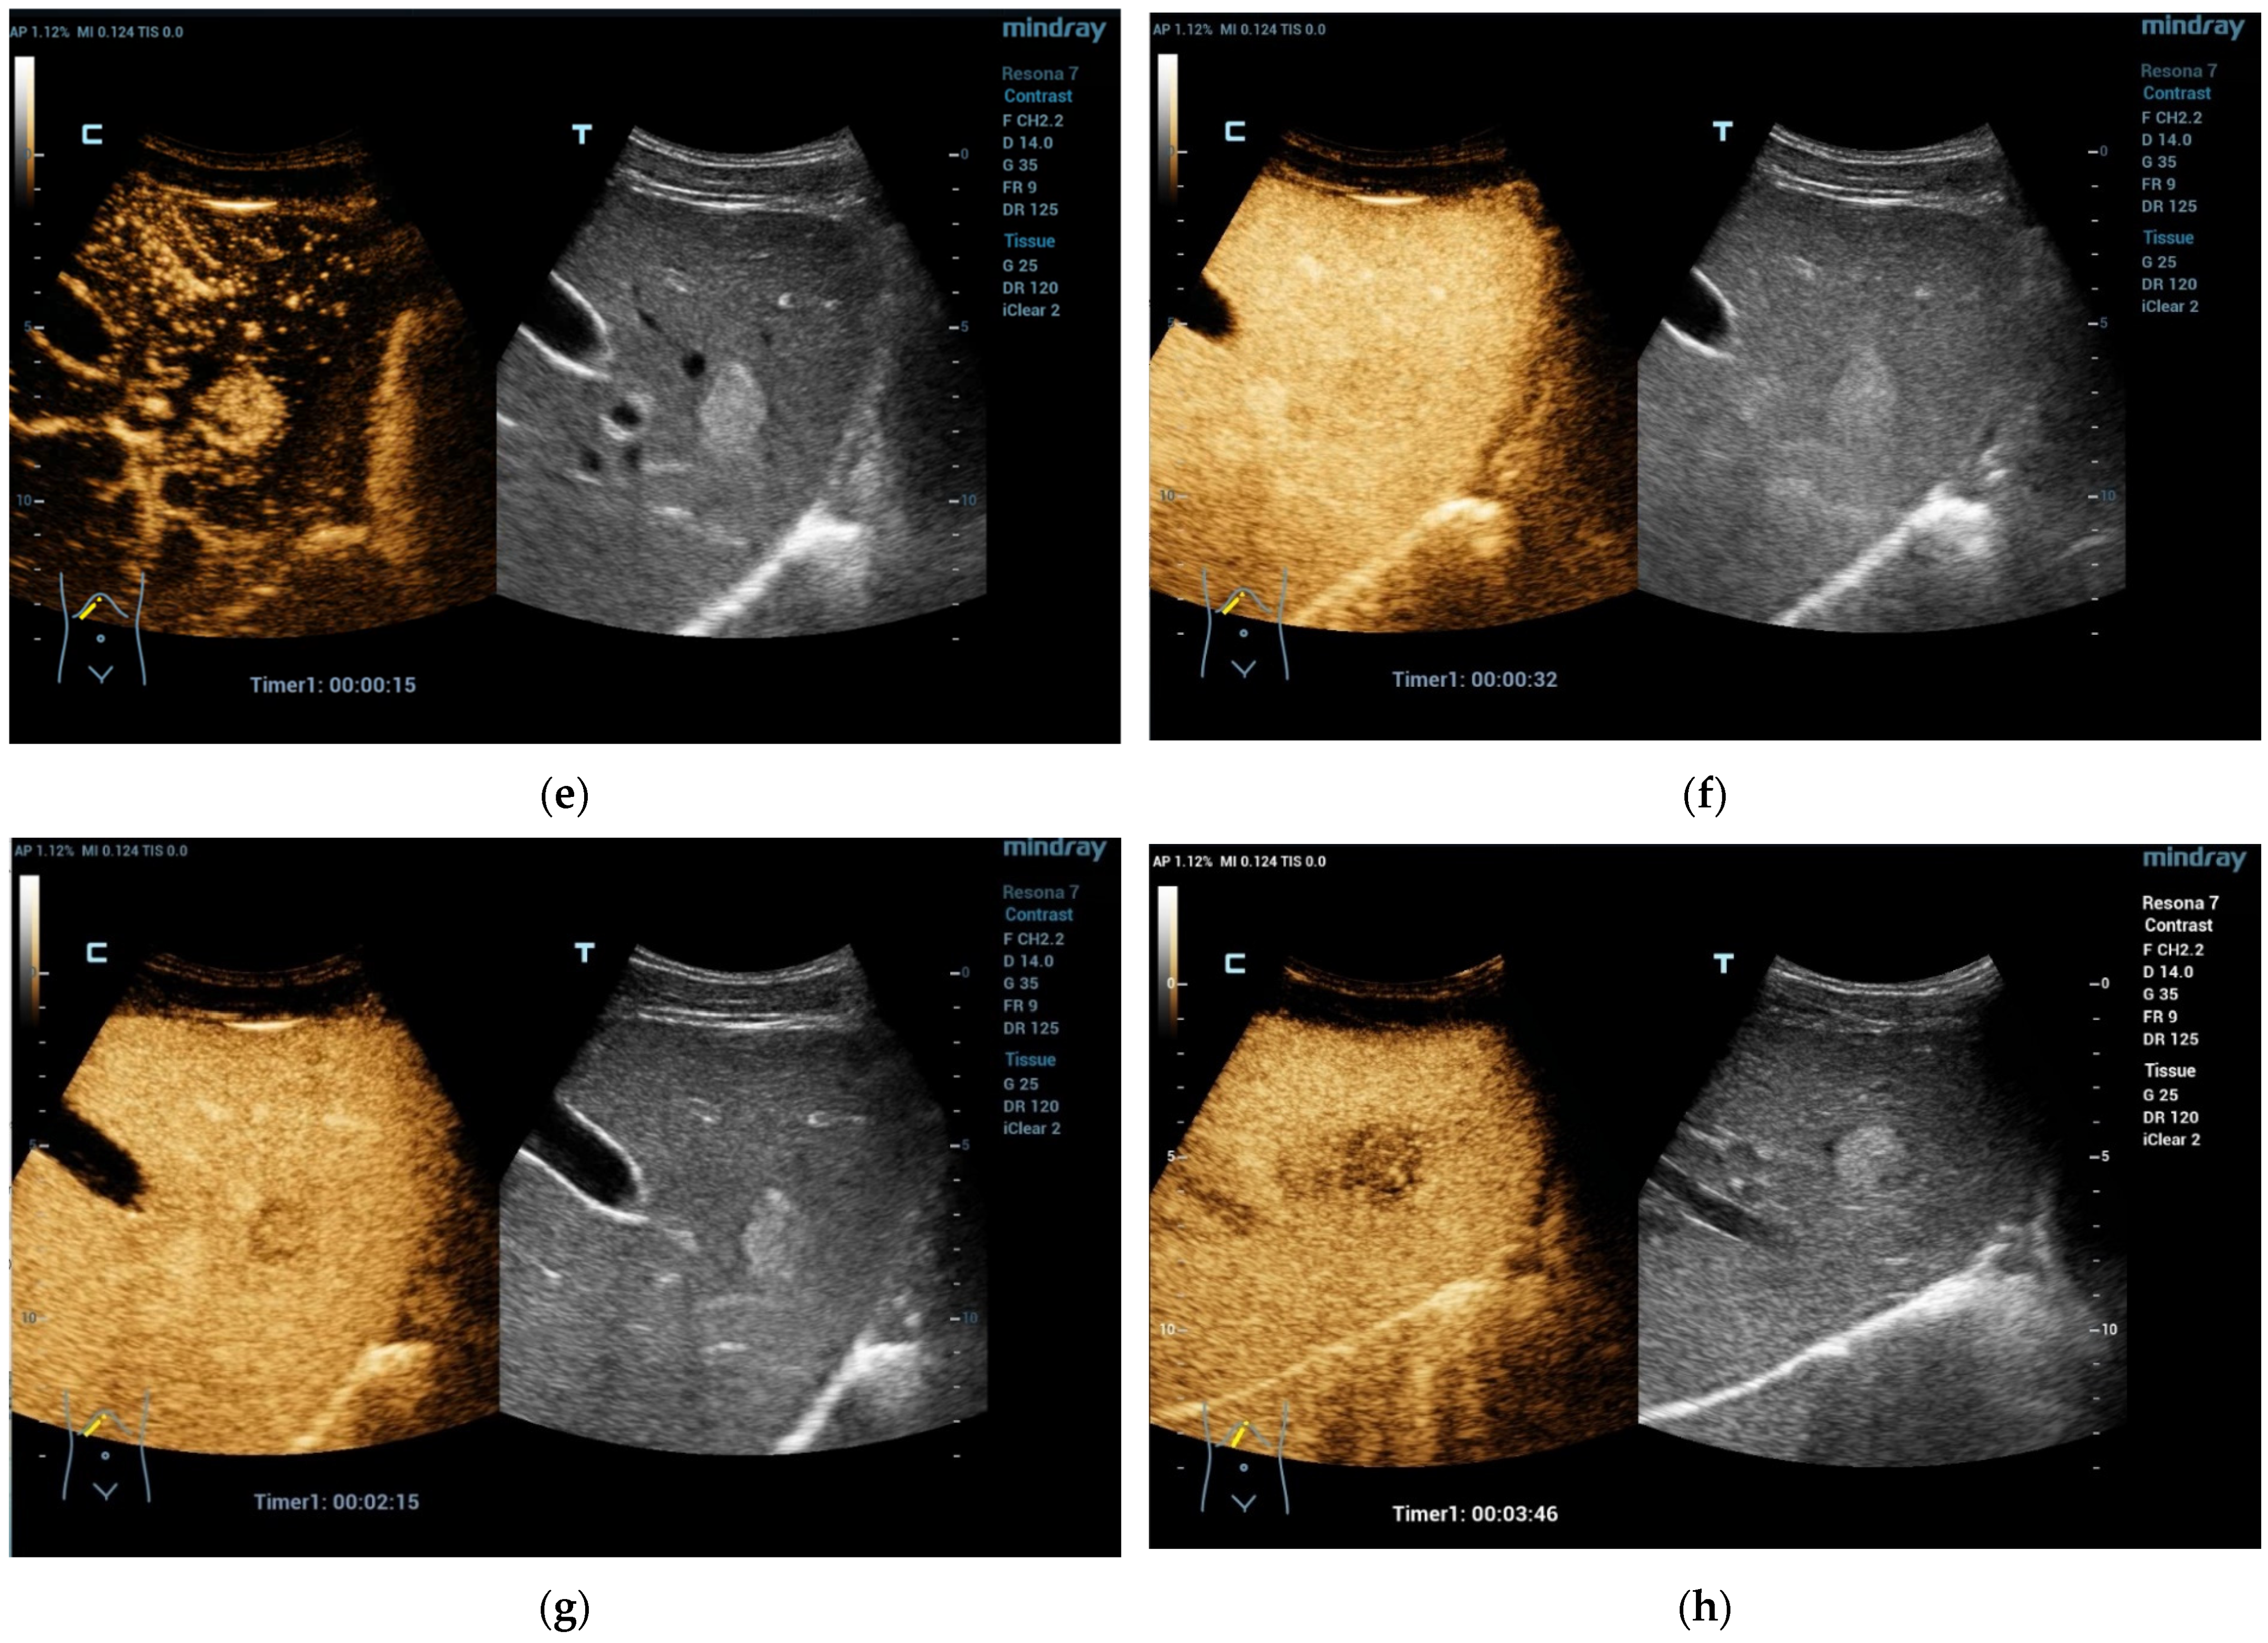

Figure 1.

A 16-year-old boy, athletic, soccer player, complaining of pain in the right lumbar–gluteal region for 10 months. MRI showed a large mass in the right iliac bone with protrusion to the muscles. Biopsy result is Ewing sarcoma. This mass is clearly visible on ultrasound (a). In liver B mode ultrasound revealed several foci: 26 × 23 mm echogenic with some hypoechoic rim (b) and entering vessel on Power Doppler mode (c) and 15 mm hypoechoic cystic-like (d). CEUS exam showed rapid filling (e) with early washout in the middle of the arterial phase (f). Washout progresses in the portal venous (g) and late venous phases (h). Liver metastases of Ewing sarcoma diagnosed. (SC5-1U transducer).